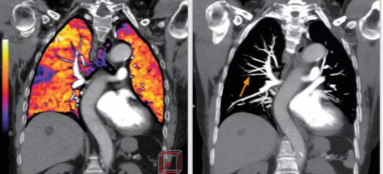

相比傳統(tǒng)成像方式,肺部柔性減影技術通過人工智能,對平掃數據和CT肺動脈血管掃描數據進行智能比對,解碼并識別各個器官(肺、氣管、肺動脈、肺靜脈、主動脈等)的空間位置,并在三維空間中進行體素級的柔性配準,從而極大提升了不同序列數據的空間位置的一致性。通過肺部柔性減影技術可得到肺強化碘圖,可以顯示出傳統(tǒng)CTPA圖像看不到的小栓塞病變,提高了栓塞檢出率,其結果甚至可與SPECT吻合。

肺智能柔性減影成像功能發(fā)現亞段肺栓塞